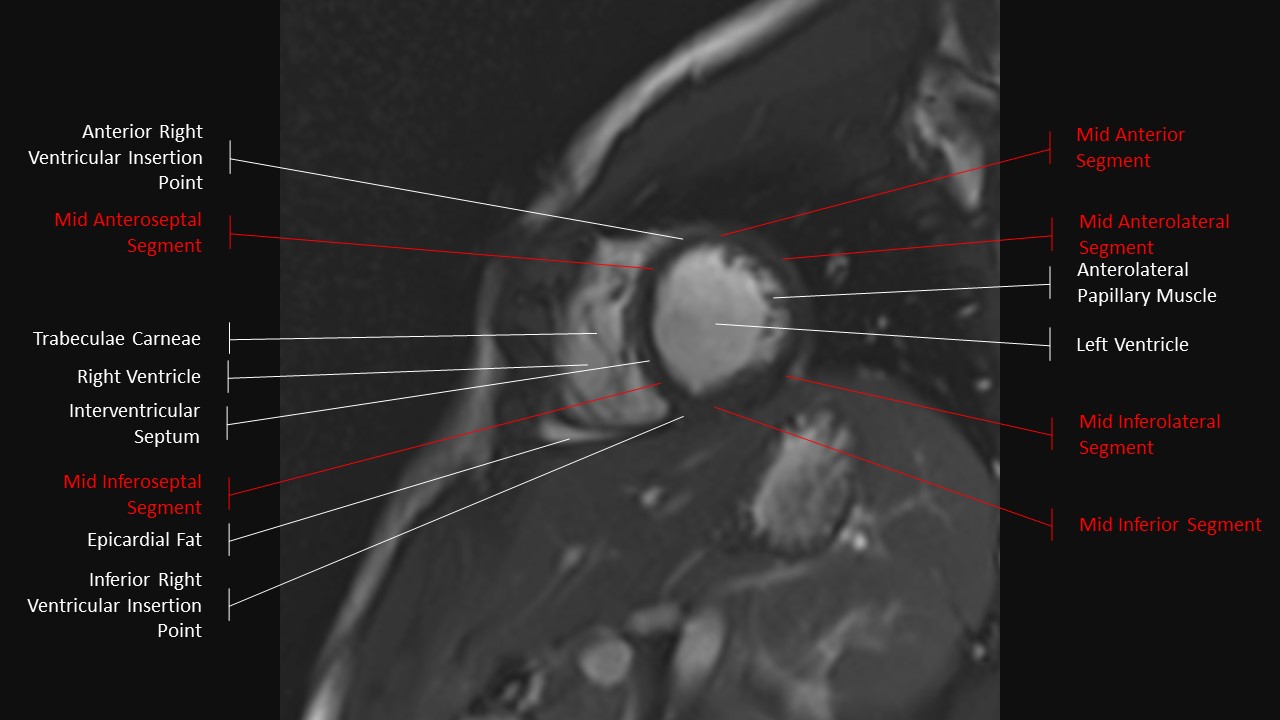

Short Axis Series